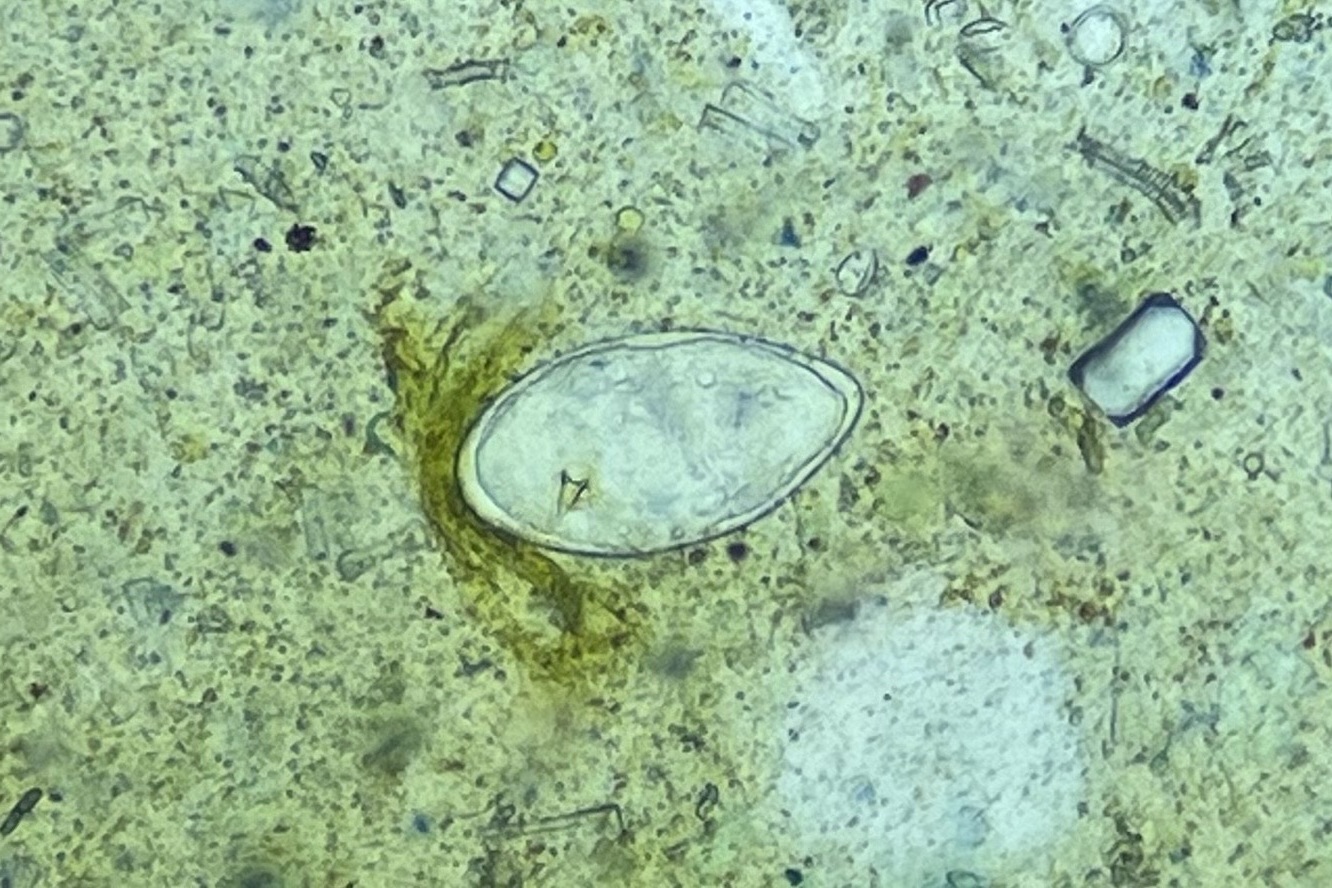

현장 실험실에서는 우리 협회 전문가와 카메룬 보건요원이 함께 검경 작업을 진행하며

전체 대변 검체 3,275건 중 1,917건(54.8%)의 기생충 감염 여부를 분석했어요.

현지 보건인력의 실무 역량을 함께 키워가는 값진 시간이었습니다!

조사 결과, 일부 보건지구에서는

주혈흡충(SCH)과 토양매개성 기생충(STH) 감염이 여전히 높은 수준으로 확인되었으며,

향후 집중 관리가 필요한 고위험 지역을 명확히 식별할 수 있었습니다.